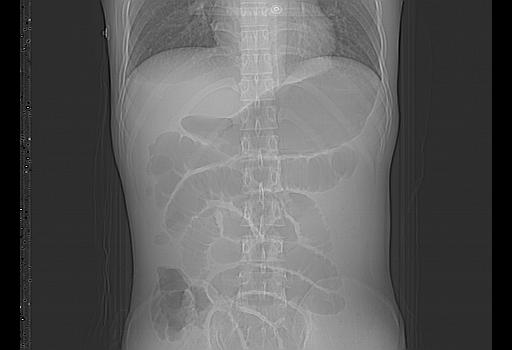

顺便请各位老师认真看看7号片

各位老师觉得胆囊是不是有点积血。我在原始片看胆囊密度不均,似有小液平面

再有就是支持楼主,胆囊7日片比5日片不仅增大许多,靠后下更见液液分层,应该是有积血。

结果收到,谢谢楼主,另外反过来看这个地方是不是游离气体影